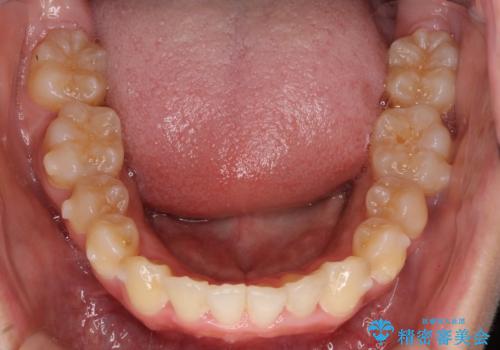

前歯のガタガタを目立たない装置でなおしたい インビザラインによる目立たない矯正

左上の前から2番目の歯が通常とは異なる形態をしており、左右対称にすることはできませんでしたが、インビザラインで周りに気づかれることなく矯正治療をおえることができ、満足していただけました。